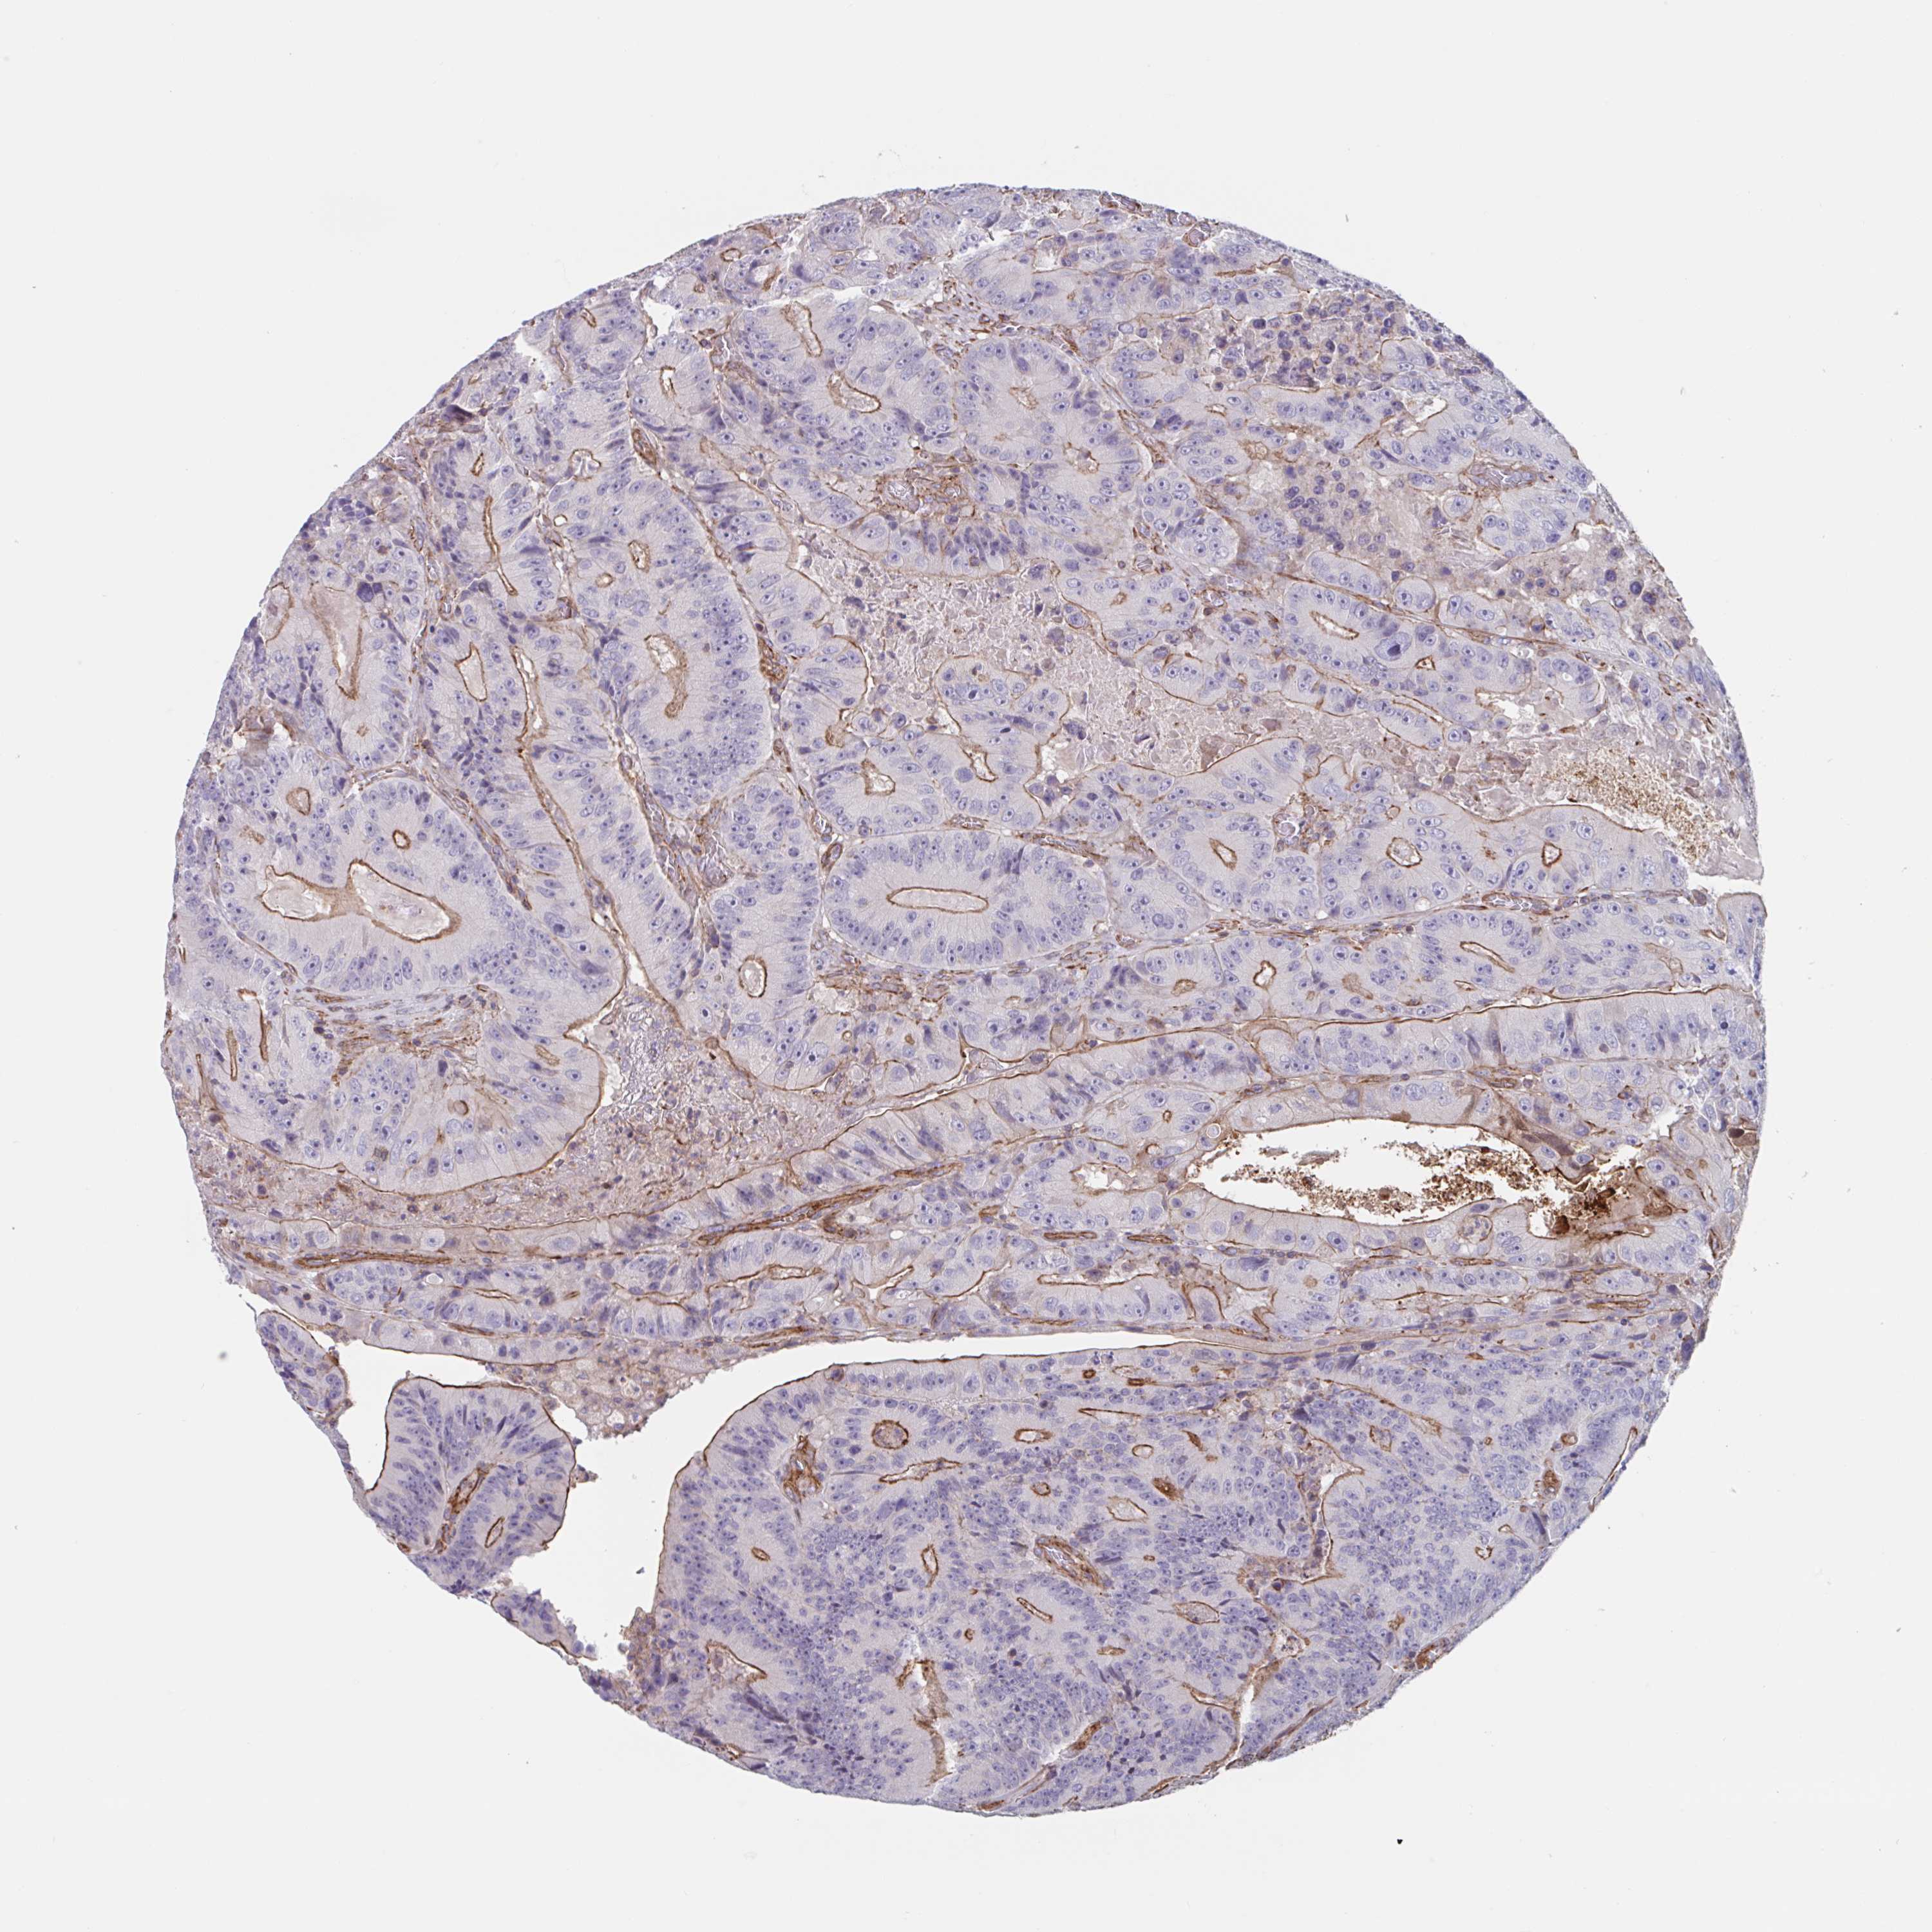

CANCER COLORECTAL CANCER Show tissue menu

Colorectal cancer

Human cancer

Colon adenocarcinoma